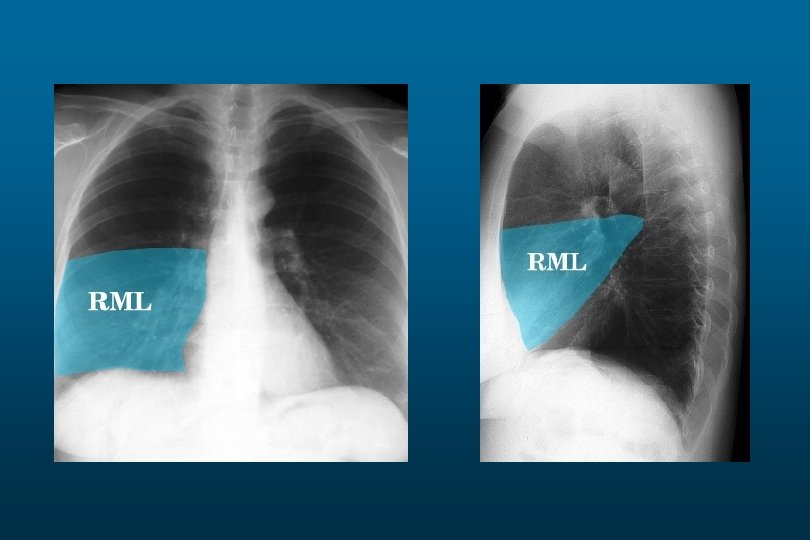

Right sided atelectasis

he right hemithorax is opaque There is a shift of the heart and trachea

he right hemithorax is opaque There is a shift of the heart and trachea away from the side ofo pacification This is characteristic of apleural effusion